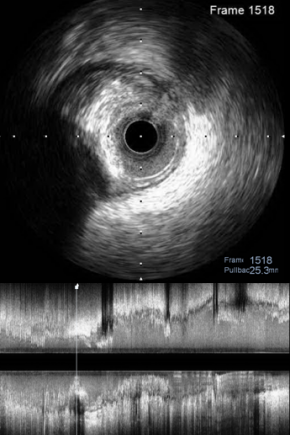

对RCA进行IVUS检查,可以看到RCA两处狭窄为纤维、钙化混合斑块,中段MLA为2.94mm²(图7);开口处MLA为4.53mm²(图8)。

图7

图8